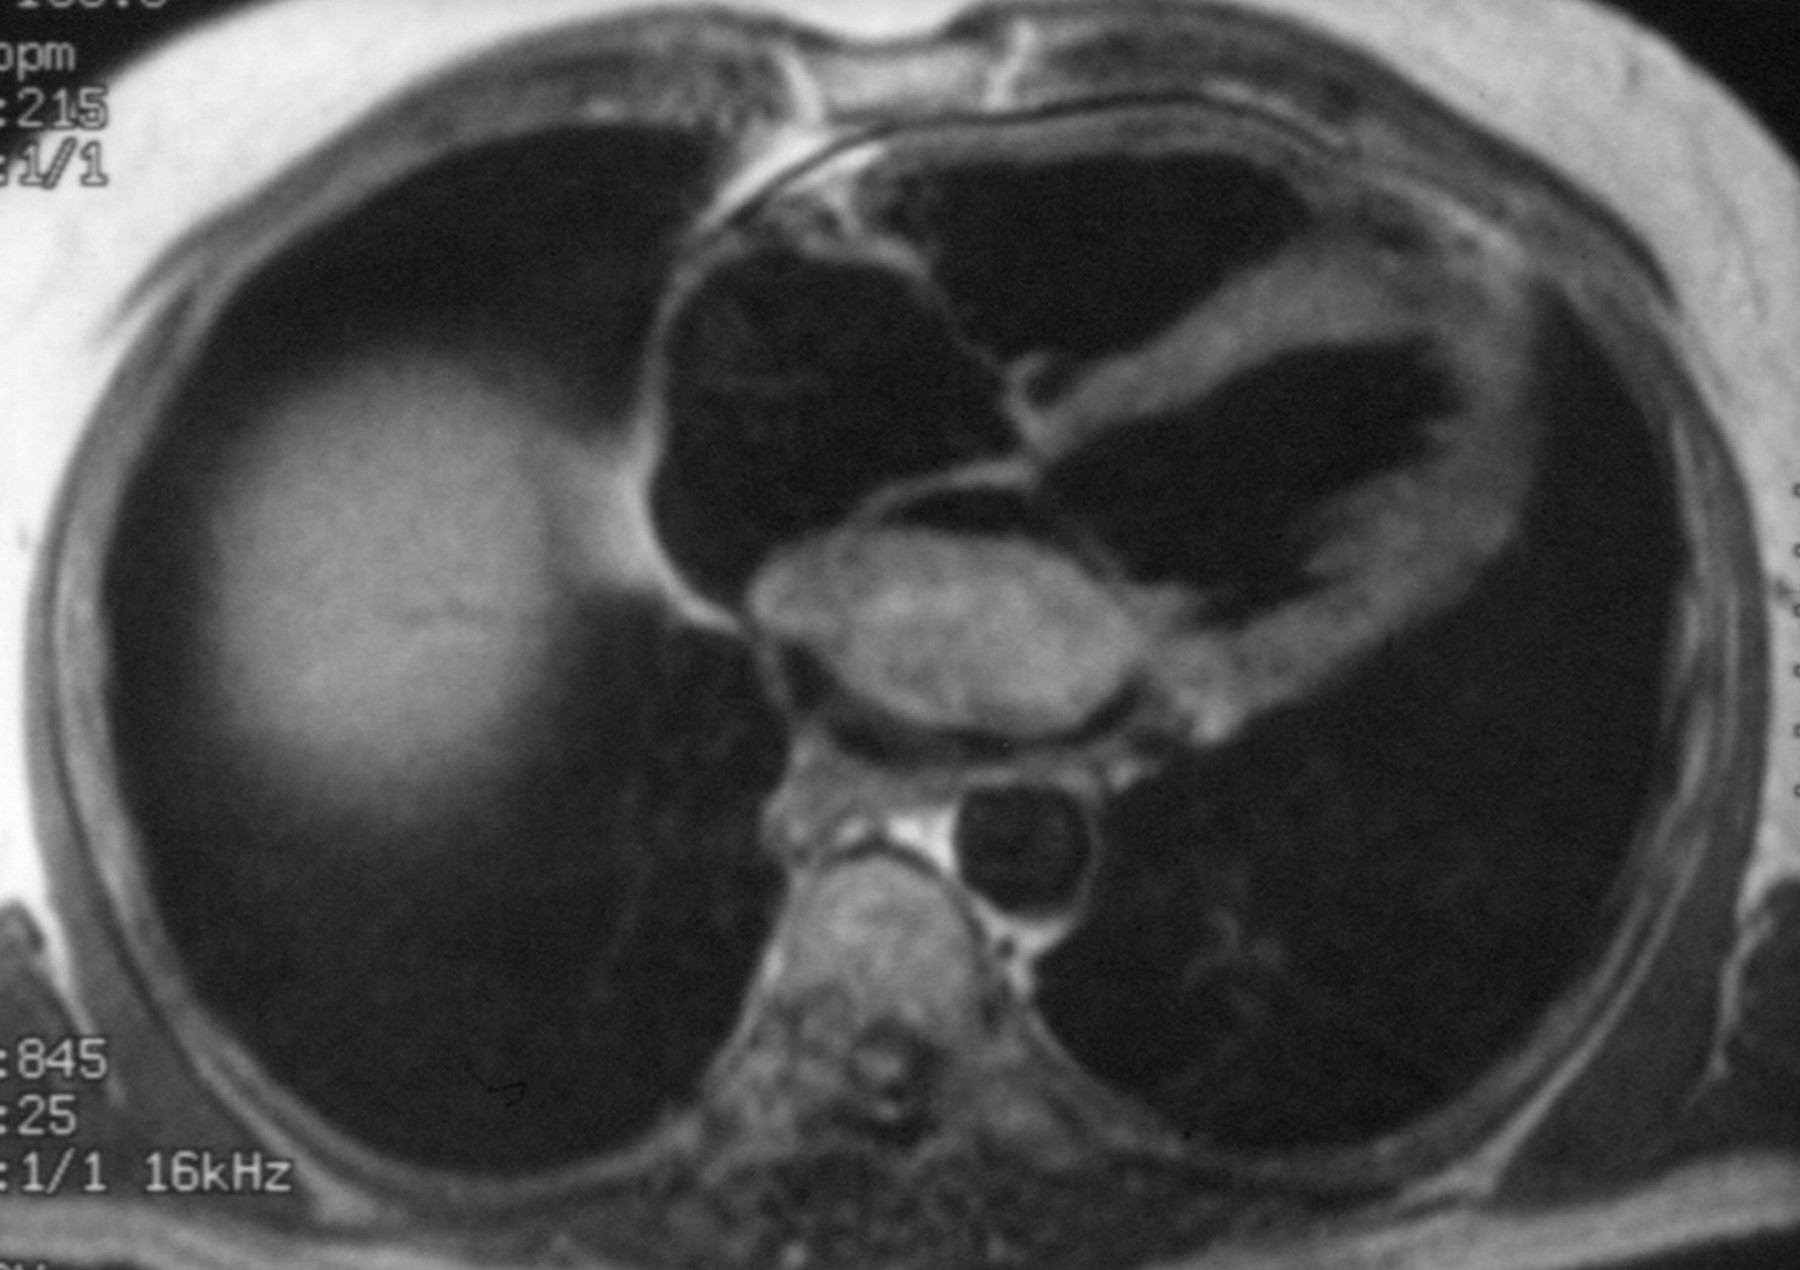

Метод эхокардиографии позволяет верифицировать диагноз. Опухоль левого предсердия вызывает появление «облачка» эхо-сигнала между створками митрального клапана во время диастолы желудочков, во время систолы он виден в полости левого предсердия. При линейном сканировании на протяжении сердечного цикла можно проследить за движением «облачка» из левого предсердия в левый желудочек и обратно. Опухоль искажает характер кривой движения передней створки митрального клапана, вызывая деформацию диастолического движения, и приводит к смещению этой створки к межжелудочковой перегородке. Плотная гладкая капсула миксомы дает четкие контуры отраженного эхо-сигнала, тогда как опухолевые массы без оболочки имеют смазанный контур. При двухмерной эхокардиографии миксо-ма видна в полостях сердца в виде более светлого образования на темном фоне, движение опухоли визуализируется на протяжении всего сердечного цикла.